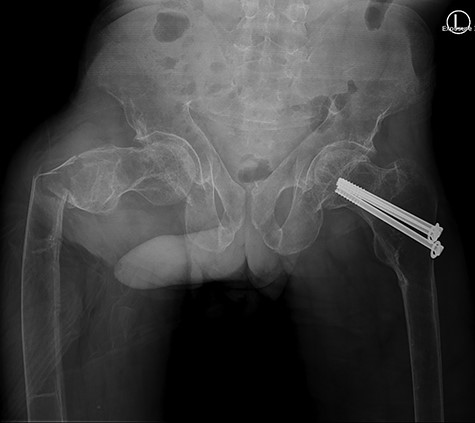

The patient was haemodynamically stable at presentation. He complained about pain in his right hip and was not able to move his right leg due to the pain. The patient was previously diagnosed with the renal Fanconi syndrome and had a previous collum femoris fracture on the left side. Conventional imaging revealed a subtrochanteric femoral fracture (Figs 1 and 2). Furthermore, contralaterally placed cannulated collum femoris screws and a severely decreased bone quality was found. No other traumatic injuries were present. Biochemical analysis showed a hypokalaemia of 3.0 mmol/l (3.5–5.0 mmol/l) and a mild hyponatraemia of 134 mmol/l (135–145 mmol/l). These findings can be related to the Fanconi syndrome.

Anterior-posterior view: right-sided subtrochanteric femoral fracture, left-sided collum femoris screws.